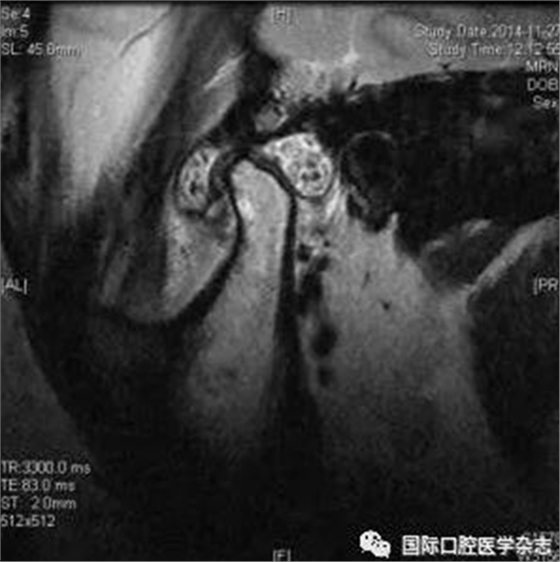

(2)不可復(fù)性關(guān)節(jié)盤前移位(圖1):多見于青壯年,往往與社會(huì)心理因素、牙合關(guān)系異常、代謝因素、偏側(cè)咀嚼、夜磨牙及不良習(xí)慣等因素相關(guān)。張口運(yùn)動(dòng)時(shí),受髁突擠壓變形的關(guān)節(jié)盤不能復(fù)位;臨床有典型的關(guān)節(jié)彈響病史,進(jìn)而彈響消失,出現(xiàn)開口受限,開口時(shí)下頜偏患側(cè)及關(guān)節(jié)區(qū)疼痛。測(cè)量被動(dòng)開口度時(shí),開口度不能增大。輔助檢查中,錐形束CT顯示關(guān)節(jié)前間隙增寬,造影片或核磁共振成像(magnetic resonance imaging,MRI)顯示不可復(fù)性關(guān)節(jié)盤前移位。

圖 1 不可復(fù)性關(guān)節(jié)盤前移位